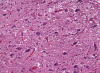

Actualmente, no hay una forma confiable de evaluar la EEB en una vaca viva. Después de que una vaca muere, los científicos pueden saber si tenía la EEB al observar su tejido cerebral bajo un microscopio y ver la apariencia esponjosa. Los científicos también pueden saber si una vaca tenía la EEB mediante el uso de kits de prueba que pueden detectar el prión anormal en el cerebro.

Cerebro de una vaca enferma con la EEB, como se ve con un microscopio usando tinciones especiales. Los grandes espacios en blanco son como los "huecos" de una esponja.

Foto cortesía del difunto Dr. Al Jenny, USDA